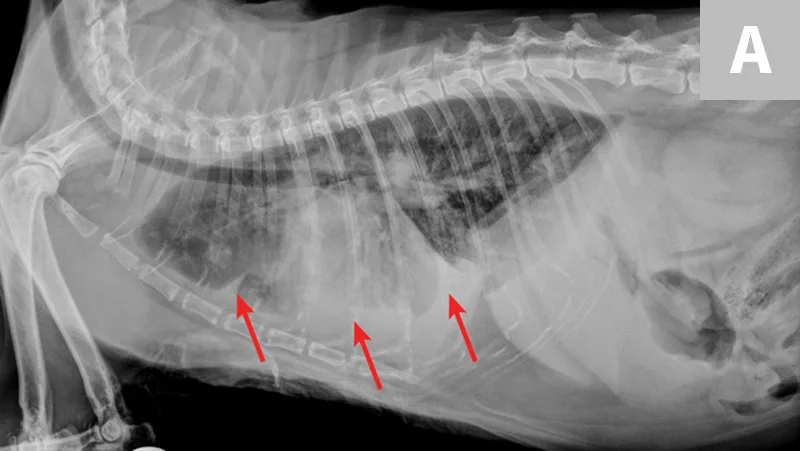

Pulmonary parenchymal infiltrates vary widely in appearance and distribution. Radiographic pulmonary changes may include lobar to multifocal alveolar disease, patchy pseudonodular appearance, peribronchial pattern, and diffuse, unstructured interstitial disease (Figure 2). Echocardiography may support a diagnosis (left atrium dimension, >15.7 mm; left atrial aortic root ratio, >1.4; E-wave velocities, >1.2).2,3

FIGURE 1A

Congestive heart failure. Note the pleural effusion (arrows).